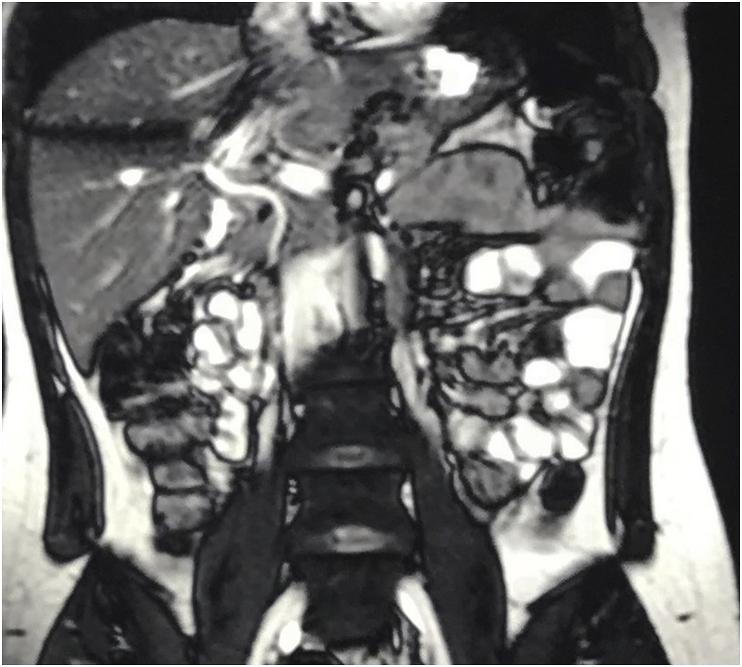

Congenital agenesis of the gall bladder is a very rare ranging from 0.02% to 0.002% in clinical practice. There is complete absence of the gall bladder with normal intra and extra hepatic biliary tree. The exact etiology remains unclear. Low index of suspicion and failure of routine investigations will result in its unexpected discovery during surgery. The condition usually results in diagnostic dilemma both before surgery and intraoperatively. A 25-year-old lady presented with repeated attacks of right side abdominal pain for 1 year. Abdominal examination showed tenderness on palpation in the right hypochonrdium. Abdominal ultrasound showed normal common bile duct with suspicion of small contacted gall bladder. MRCP showed extrahepatic biliary tree and not visualized gall bladder. During diagnostic laparoscopy exploration of the whole peritoneal cavity was performed. The gall bladder was not visualized after complete visualization of biliary anatomy. The appendix was inflamed with multiple adhesions with the bowel. The cecum was high placed in the sub-hepatic region. Laparoscopic appendicectomy was performed. Patients with gall bladder agenesis surprisingly have symptoms similar to cholecystitis, the pain may be attributed to cholangitis, biliary stones, or sphincter of Oddi dysfunction. When the condition diagnosed at operation extensive dissection to identify the gall bladder must be avoided because it may result in biliary injury.

先天性胆囊缺如是一种非常罕见的疾病,在临床实践中的发生率为0.02%至0.002%。胆囊完全缺失,肝内和肝外胆管树正常。确切病因尚不清楚。怀疑指数低和常规检查失败会导致在手术期间意外发现该病。这种情况通常会在手术前和手术中导致诊断困境。一名25岁女性因右侧腹痛反复发作1年前来就诊。腹部检查显示右季肋部触诊有压痛。腹部超声显示胆总管正常,怀疑有小的收缩胆囊。磁共振胰胆管造影(MRCP)显示肝外胆管树,未显示胆囊。在诊断性腹腔镜检查中,对整个腹腔进行了探查。在完全观察到胆管解剖结构后,未发现胆囊。阑尾发炎,与肠管有多处粘连。盲肠高位位于肝下区域。进行了腹腔镜阑尾切除术。胆囊缺如的患者令人惊讶地出现与胆囊炎相似的症状,疼痛可能归因于胆管炎、胆结石或Oddi括约肌功能障碍。当在手术中诊断出这种情况时,必须避免进行广泛的解剖以寻找胆囊,因为这可能导致胆管损伤。